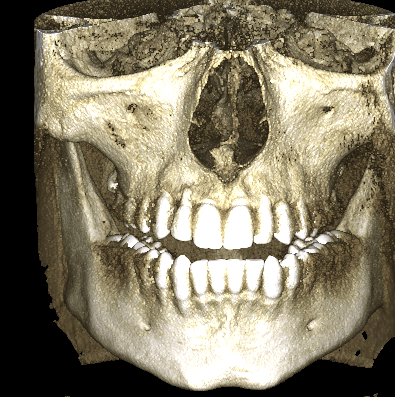

I have subhuman smile, I barely show any upper teeth when smiling, so got 3d scan done and results say a lot.

This is My Skull:

my maxilla itself isn't really short but bone above upper teeth specifically Alveolar process of the maxilla is extremely short compared to normal.

Im like perfect fucking candidate for lefort 1